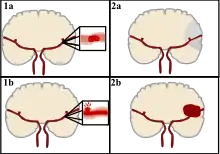

Stroke can be classified into two major categories: ischemic and hemorrhagic.[19] Ischemic stroke is caused by interruption of the blood supply to the brain, while hemorrhagic stroke results from the rupture of a blood vessel or an abnormal vascular structure. About 87% of stroke is ischemic, with the rest being hemorrhagic. Bleeding can develop inside areas of ischemia, a condition known as "hemorrhagic transformation." It is unknown how many cases of hemorrhagic stroke actually start as ischemic stroke.[2]